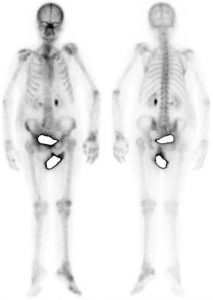

Algodystrophie post-AVC

AVC ischémique choroïdien antérieur droit en mai 2015.Hémiplégie gauche.

Apparition de douleurs de l’épaule et du genou gauche avec aspect inflammatoire local.

Au temps tissulaire :

Hyperhémie diffuses de l’ensemble du membre supérieur gauche et du membre inférieur gauche.

Au temps tardif :

Hyperfixation diffuse de l’ensemble du membre supérieur gauche et de l’ensemble du membre inférieur gauche.

Algodystrophie des membres supérieur et inférieur gauche post-AVC